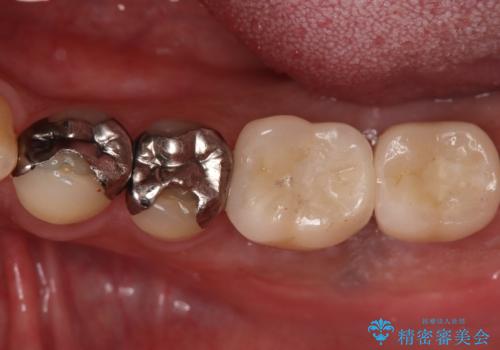

今回の治療では、まず左下6番と7番の欠損部に、骨の状態を考慮しながら慎重に2本のインプラントを埋入しました。インプラント体と骨がしっかりと結合するのを待った後、最短の期間で最終的な被せ物を装着するための精密な型取りを実施。最終的に、周囲の歯と調和した審美性の高いセラミック製の歯を装着しました。

治療期間は約3ヶ月で完了。以前の入れ歯のような煩わしさや動く心配がなくなり、天然歯と変わらない強い力でしっかりと食べ物を噛み砕けるようになり、快適な食生活を取り戻していただけました。